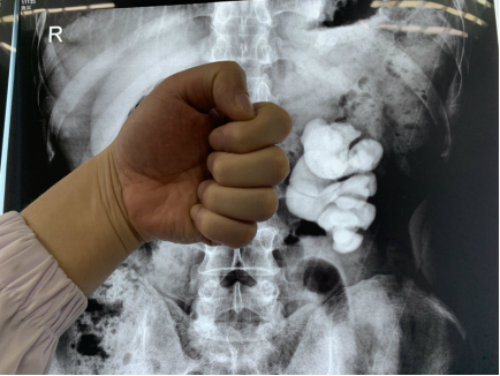

2019年11月26日,湖北蘄春的周先生在武漢京都結(jié)石醫(yī)院成功保腎取出左腎里近十公分的拳頭大結(jié)石,堪稱微創(chuàng)取石領(lǐng)域的典范案例。

跟絕大多數(shù)腎結(jié)石患者一樣,周先生在發(fā)現(xiàn)結(jié)石之前,沒(méi)有體檢的習(xí)慣,偶爾的腰脹腰痛問(wèn)題,也總在當(dāng)腰椎病在治。結(jié)果差點(diǎn)把腎給“耽誤”了。

據(jù)他本人回憶,最早發(fā)現(xiàn)左腎被結(jié)石撐滿是在11月3日,當(dāng)?shù)亟釉\醫(yī)生叫他做好手術(shù)準(zhǔn)備,隨時(shí)可能要切腎。不相信問(wèn)題嚴(yán)重性的他又找到另外一位醫(yī)生,當(dāng)?shù)诙会t(yī)生也給出了同樣的答復(fù)后,他開(kāi)始心灰意冷了。

近日,周先生慕名趕到專門治結(jié)石的武漢京都結(jié)石醫(yī)院。完善相關(guān)檢查后,醫(yī)生初步判定其左腎還有部分功能,決定為他放手一搏。盡管手術(shù)難度大,術(shù)中出現(xiàn)大出血和腎內(nèi)壓過(guò)高導(dǎo)致的穿刺時(shí)腎破裂的概率極高,但在該院多科室專家的全力救治下,周先生最終如愿保住了左腎,拳頭大的結(jié)石也被處理了。

醫(yī)生提醒,腎結(jié)石和腰椎病癥狀有相似之處,市民如無(wú)法自行判斷,可到專業(yè)醫(yī)院做泌尿系彩超、腰椎ct等加以區(qū)分,切勿顧此失彼。